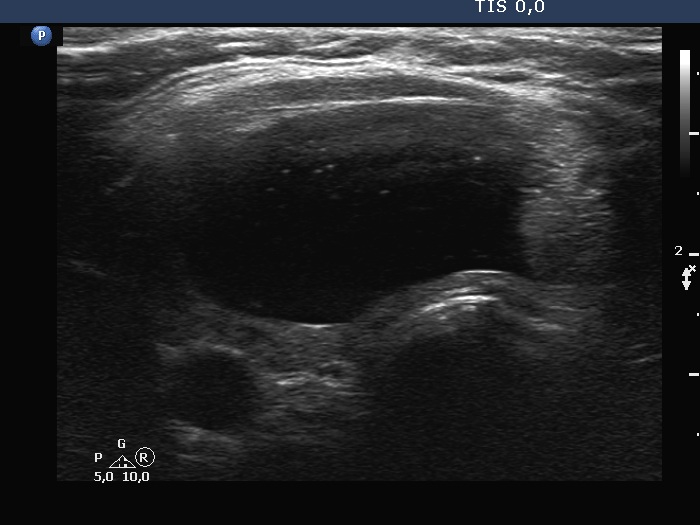

Follow-up investigation 6 years later (ultrasonographic picture 5)

Right lobe, longitudinal scan